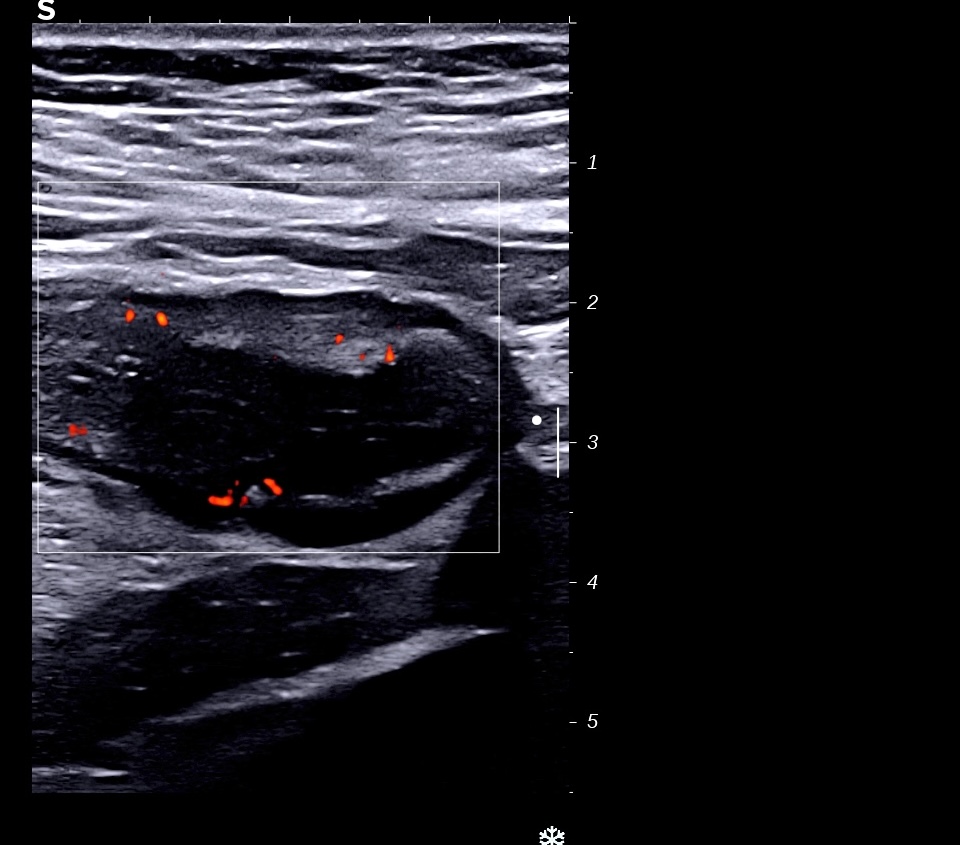

Paroi totalement hypoéchogène et couple longitudinale, surface irrégulière donc ulcérée

Paroi antérieure et postérieure accolées, hypoéchogènes

*Paroi antérieure et postérieure accolées, hypoéchogènes et doppler *

Surface irrégulière ulcérée